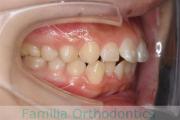

歯並びが悪いのを治したい、ということで来院されました。下顎の後退が強く、厳しい上顎前突(出っ歯)の状態でしたが、歯科上下左右から小臼歯を抜歯して、マルチブラケット装置により治療を行いました。2年強、25回程度の通院をしていただきました。上の前歯の移動量が大きく、歯根吸収の発生リスクが高めのケースです。